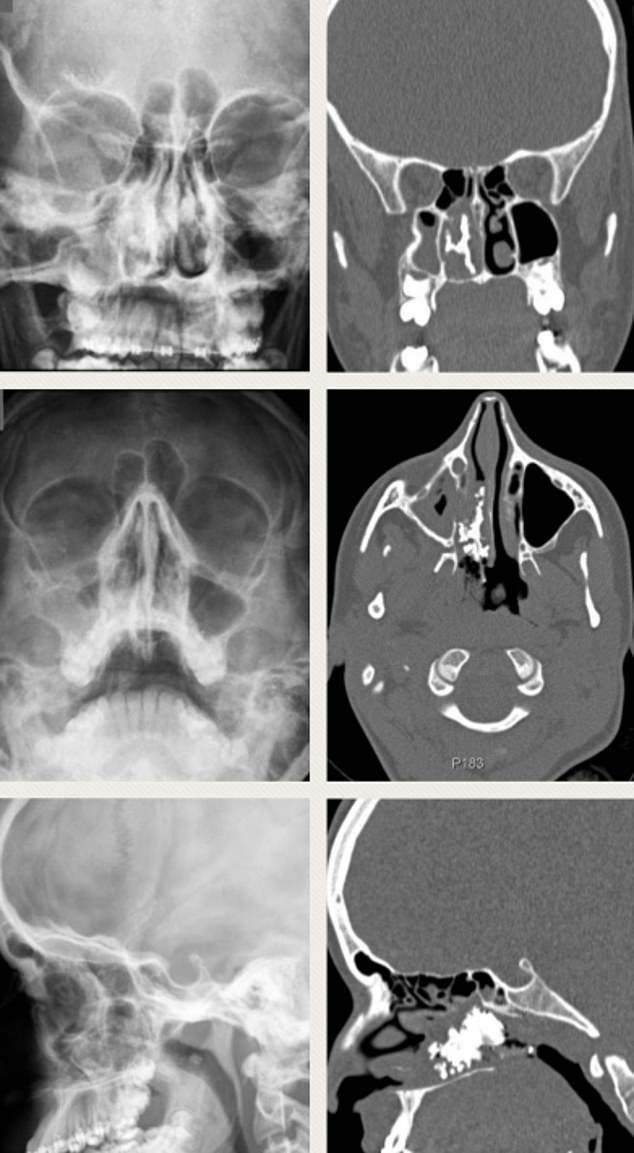

Sau khi chụp X-quang và CT, các bác sĩ đã phát hiện ra rằng có một vật thể lạ trong xoang mũi của cô gái. Hình ảnh quét CT cho thấy đây là “một vật thể lớn, có hình dạng bất thường, bao gồm nhiều gai và cánh”, được các bác sĩ mô tả giống như “đá san hô”.

Một người đàn ông 59 tuổi đã tìm đến đơn vị Tai mũi họng tại Bệnh viện Đại học Aarhus sau nhiều năm nghẹt mũi và mất khứu giác, cũng như tiết dịch trắng sữa.

Sau khi thực hiện quét và kiểm tra xem cái gì đang phát triển trong lỗ mũi anh ấy, các bác sĩ đã phát hiện ra đó là một chiếc răng nguyên vẹn và thực hiện loại bỏ nó.

Việc phát triển một chiếc răng trong lỗ mũi là rất hiếm, và được cho rằng xuất hiện trong khoảng 0.1% đến 1% dân số thế giới, nhưng có thể ít người nhận ra tình trạng này.

Sự tăng trưởng kì lạ này được gọi là “răng giữ lại nội sọ”, có thể được gây ra bởi những ảnh hưởng vật lí hoặc vấn đề khi phát triển, nhưng trong trường hợp này, các bác sĩ không thể tìm ra một lời giải thích thỏa đáng.